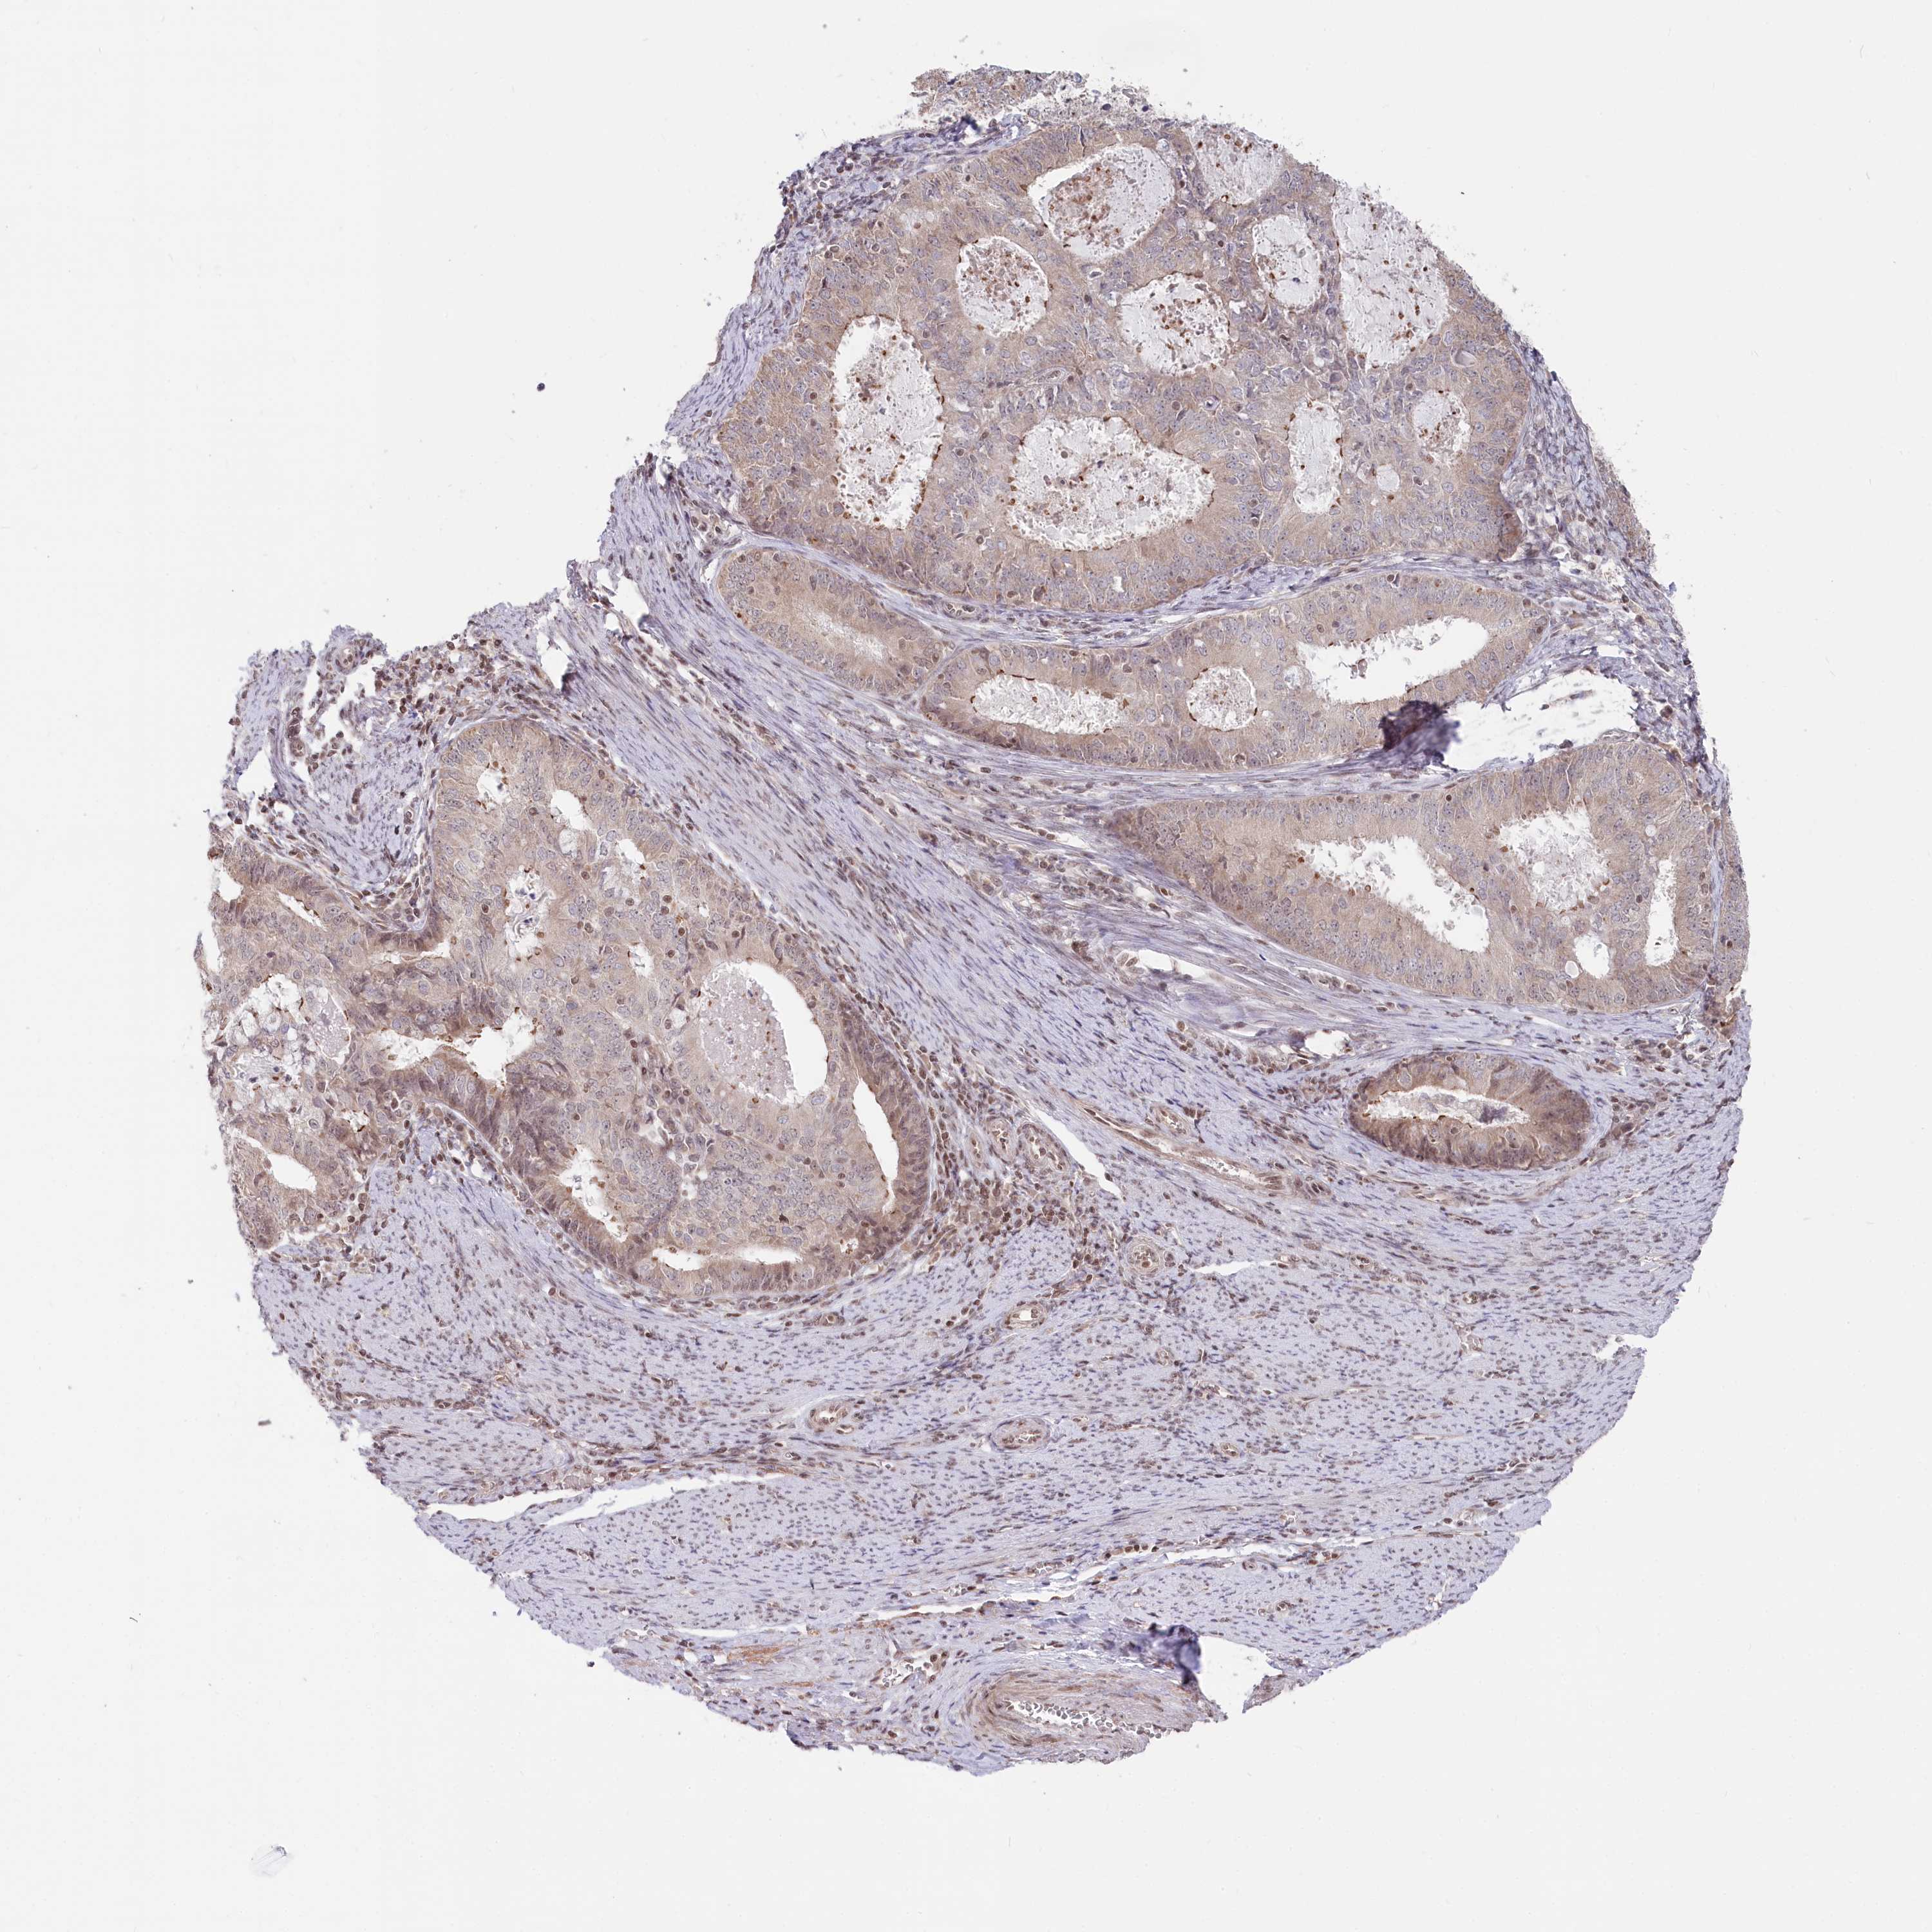

ENDOMETRIAL CANCER - Protein expressioni

A mouse-over function shows sample information and annotation data. Click on an image to view it in a full screen mode. Samples can be filtered based on level of antibody staining by selecting one or several of the following categories: high, medium, low and not detected. The assay and annotation is described here.

Note that samples used for immunohistochemistry by the Human Protein Atlas do not correspond to samples in the TCGA dataset.

Antibody stainingi

Antibody staining in the annotated cell types in the current human tissue is reported as not detected, low, medium, or high, based on conventional immunohistochemistry profiling in selected tissues. This score is based on the combination of the staining intensity and fraction of stained cells.

Each image is clickable and will lead to virtual microscopy that enables deeper exploration of all samples and also displays staining intensity scores, fraction scores and subcellular localization as well as patient and tissue information for each sample.

Antibody HPA035568

Antibody HPA037017

Staining

High

Medium

Low

Not detected

Intensity

Strong

Moderate

Weak

Negative

Quantity

>75%

75%-25%

<25%

None

Location

Nuclear

Cytoplasmic/membranous

Cytoplasmic/membranous,nuclear

Adenocarcinoma, NOS